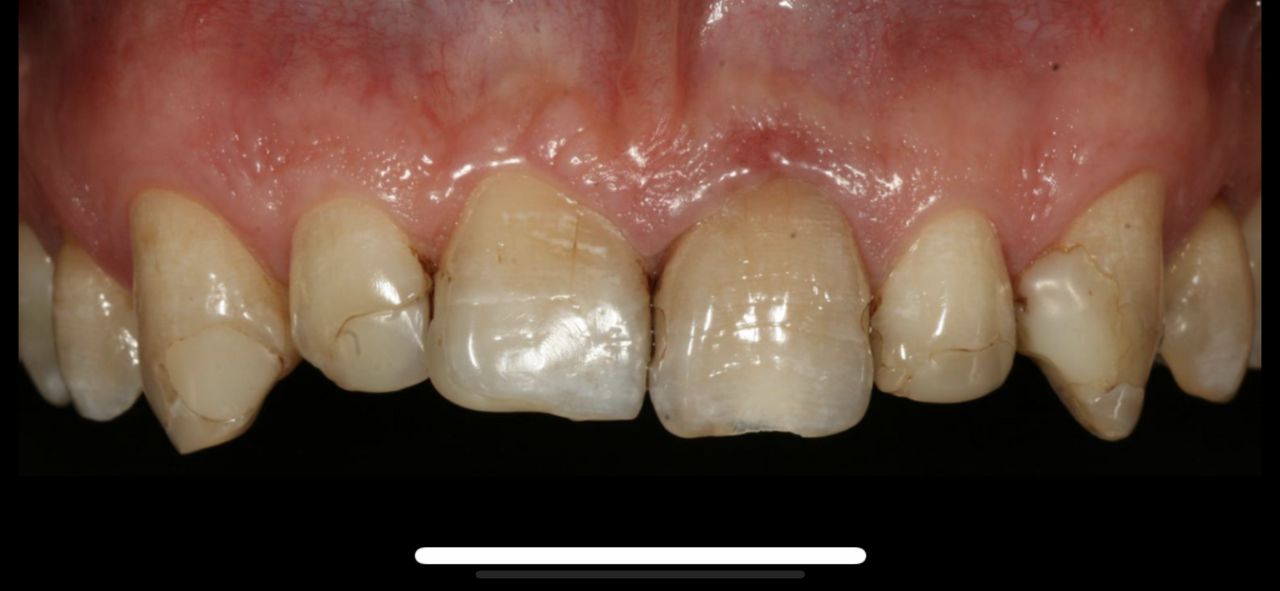

Ukończyłem Łódzką Akademie Medyczna, na wydziale stomatologicznym . W 2007 roku uzyskałem tytuł specjalisty w dziedzinie protetyki stomatologicznej. Regularnie pogłębiam wiedze z zakresu stomatologii o czym świadczą zdobyte przeze mnie certyfikaty . W chwili obecnej prowadzę NZOZ Duodent , specjalistyczny gabinet protetyczny na Widzewie - wschodzie , przy ul. Gogola 12 . Znajdują sie tu trzy nowocześnie urządzone i wyposażone gabinety stomatologiczne. Pracujemy na sprzęcie Sterna Webera, prestiżowej szwajcarskiej firmy produkującej unity stomatologiczne...W gabinecie znajduje sie skaner wewnątrzustny MEDIR i 500 R , gdyz obecnie gabinet nasz wyspecjalizował sie w PROTETYCE CYFROWEJ

. W tym wypadku odległość nie ma znaczenia , gdyż wyciski w formie cyfrowej trafiają internetem do pracowni w ciągu paru sekund po ich uzyskaniu drogą skanowania w ustach pacjenta, bez zniekształceń i deformacji. CAD/CAM to supernowoczesna frezarka komputerowa, wycinająca z bloczku cyrkonu najbardziej precyzyjne elementy .

• Korony cyrkonowe

Od 1 600 zł

Z pełnym przekonaniem polecam leczenie protetyczne w tym gabinecie. Wykonane korony porcelanowo-cyrkonowe spełniły moje oczekiwania zarówno pod względem estetycznym, jak i funkcjonalnym. Efekt końcowy jest bardzo naturalny, korony są idealnie dopasowane i komfortowe w codziennym użytkowaniu. Cały proces leczenia przebiegał sprawnie, z dokładnym omówieniem planu oraz poszczególnych etapów. Lekarz wykazał się dużą wiedzą, precyzją i dbałością o detale, co w protetyce ma kluczowe znaczenie. Dodatkowo czułem się zaopiekowany i spokojny, co zdecydowanie podnosi komfort leczenia.

• Duo-Dent korony cyrkonowe  •